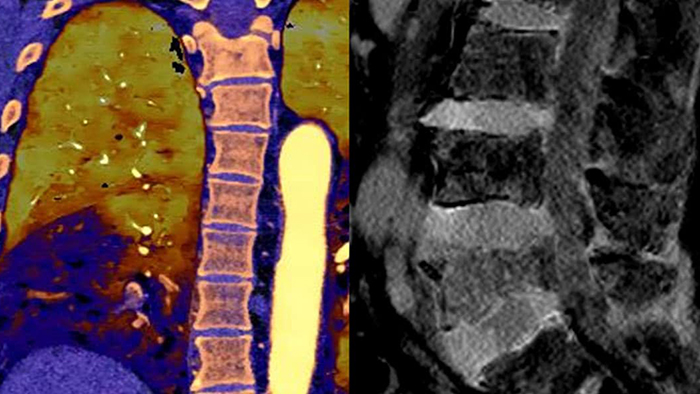

Vá além da CT convencional. Veja de que forma os vários tipos de resultados obtidos com deteção espectral podem aumentar a fiabilidade do seu diagnóstico.